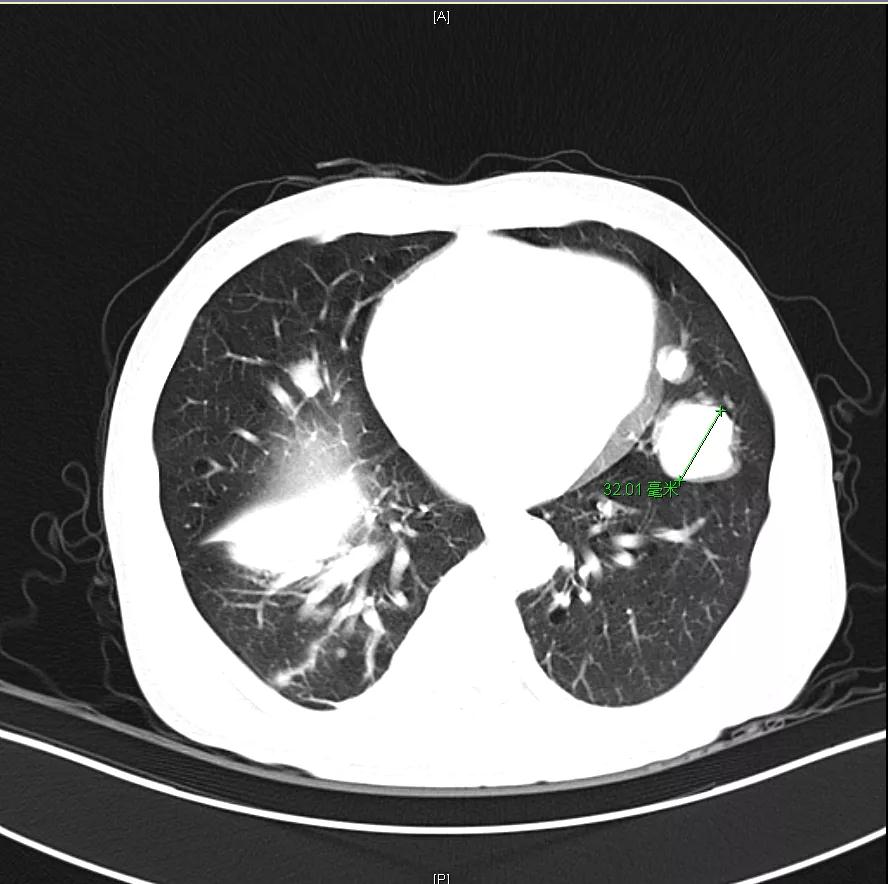

用药6个月后:肝脏病灶明显缩小,子灶消失,仅有少量动脉期强化;肺转移单个持续缩小稳定,PET CT活性弱;HBV DNA 转阴;可考虑转化切除。

术后末次随访2021年12月6日,肝内未见明显病灶,肺部病灶稳定1.3cm。

目前OS 17个月,RFS 10个月。